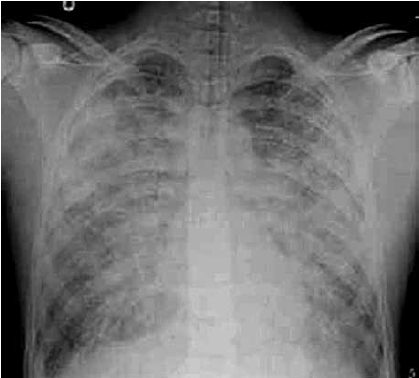

Analise o caso clínico a seguir para responder à questão abaixo:

Você é chamado para discutir o caso de um paciente internado na UTI há 3 dias, com diagnóstico de síndrome do desconforto respiratório agudo (SDRA), em ventilação mecânica de difícil manejo. Histórico: Paciente masculino, de 27 anos de idade, hipertenso e dislipidêmico, busca atendimento hospitalar devido a febre, tosse e dispneia há 3 dias. Na admissão, apresentava-se com sinais de choque séptico e franca insuficiência respiratória. Na ausculta pulmonar, estertores creptantes presentes difusamente. O paciente foi encaminhado à UTI e submetido à ventilação mecânica, além de suporte clínico e prescrição farmacológica.

Parâmetros da ventilação mecânica atual: modo: ventilação assistida controlada; ciclagem: volume controlada; volume corrente: 6 mL/Kg; PEEP: 12 cm H2O; FiO2: 70%; FR: 30 ipm;relação. Inspiração: expiração: 1:1; pressão de Platô: 30 cm H2O. Última gasometria: pH 7,22; PaO2 62 mmHg; PaCO2 69 mmHg; BE: –1,4 mmol/L; SaO2 86%; bicarbonato 20 mEq/L.

Exame de imagem:

(Disponível em: https://resources.wfsahq.org/ atotw/sindrome-do-desconforto-respiratorio-agudo/)

Considerando a patogênese da SDRA grave, qual alternativa justifica a dificuldade no manejo ventilatório desse paciente?